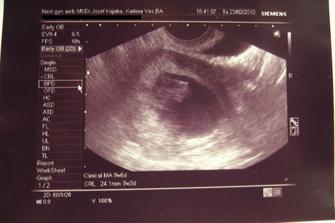

♥ 03.02.2010 sme boli u uja doktora a potvrdil nám vitalitu plodíku. Meriame 18mm a všetko je tak ako má byť. Vzali nám krvičku a o 10 dní ideme na ďalší kontrolný ultrazvuk